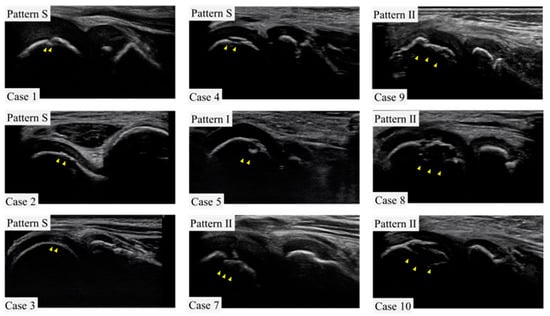

Those with complaints of elbow pain and joint tenderness were considered symptomatic. Physical examination revealed pain in 19 players, including 2 who were part of Group O. There was limited extension observed in eight players, half of whom belonged to Group O. Pain during extension was present in five players, with two being from Group O. Limited flexion was found in eight players, with two in Group O; pain on flexion was noted in four players, with none in Group O. Tenderness at the medial epicondyle was evident in 27 players, with 3 in Group O, while tenderness at the humeroradial joint was reported in 10 players, including 1 in Group O. Furthermore, tenderness at the olecranon was found in five players, with one from Group O. The valgus stress test was positive at 30 degrees of elbow flexion in 13 players, with 1 in Group O; at 60 degrees, it was positive in 16 players, with none in Group O; and at 90 degrees, it was positive in 13 patients, with none in Group O (Table 1). Of those diagnosed with OCD, five exhibited pattern S, one had pattern 1, and four presented with pattern 2 (Figure 4).

Figure 4. Ultrasound images of the lateral elbow for each case in this study. For one case (case 6), only the record was available, and the image was not preserved. Arrowheads indicate sites of OCD.